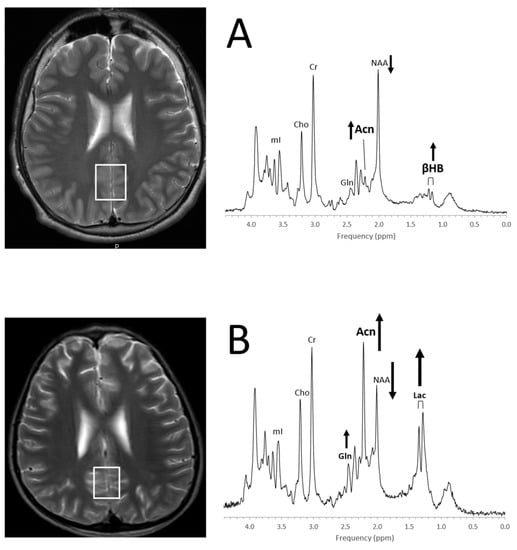

- Seymour, K.J.; Bluml, S.; Sutherling, J.; Sutherling, W.; Ross, B.D. Identification of cerebral acetone by 1H-MRS in patients with epilepsy controlled by ketogenic diet. Magma 1999, 8, 33–42. [Google Scholar] [PubMed]

| Acetone (Acn) | Produced by decarboxylation of acetoacetate, singlet at 2.22 ppm more readily detectable than βHB (see below) | Disease correlate unknown | Ketosis |

| β-Hydroxybutyrate (βHB) | Produced by the decarboxylation of acetoacetate, doublet similar to lactate but at 1.19 ppm | Disease correlate unknown | Ketosis |